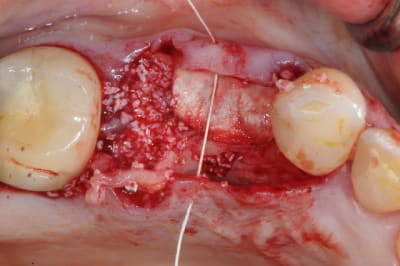

pour débuter ce post je propose un petit cas avec une ROG un comblement alvéolaire et un lambeau pédiculé pour fermer le site d'extraction.

un petit exemple de ce matin: extraction des piliers 12 et 14, curetage, comblement avec du bio-oss de la dépression osseuse vestibulaire au niveau de l'inter 13, comblement des alvéoles 12 et 14 au genos et recouvrement par 2 pédicules conjonctifs. Temporisation avec un partiel amovible.